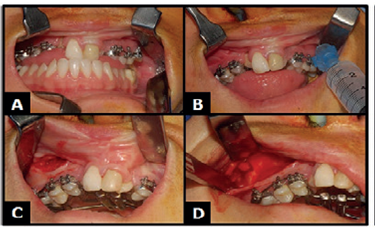

Por fim, realizou-se irrigação da cavidade bucal com soro fisiológico, aspiração, sutura dos retalhos com fio Vicryl 4-0 e remoção do tampão orofaríngeo (Figura 6A).

A) Sutura.

Figura 6: A) Sutura.

Fonte: Documento obtido durante o estudo.

O acionamento do aparelho expansor passou a ser realizado após o terceiro dia pós-operatório, com ativação de 2/4 de volta pela manhã e 2/4 no período da tarde até o esgotamento do parafuso.

Mediante o término da expansão teve início o período de contenção, durante o qual o paciente permaneceu por 4 meses com o parafuso expansor estabilizado e mantido em posição com uso de resina acrílica, além de mais 2 meses adicionais utilizando a placa de Hawley.